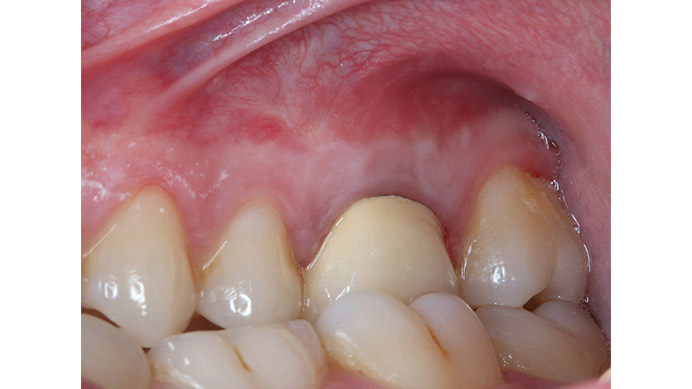

Ian es un paciente que nos cuenta su experiencia tras una intervención de cirugía periapical. Ian vino a la clínica dental IDIM con molestias en una muela superior que en el estudio radiográfico se vio que presentaba infección a causa del fracaso de una endodoncia.

Se decidió realizar una cirugía periapical para eliminar la infección y sellar las raíces con un empaste para evitar que volviera a tener problemas. Gracias a esta efectiva intervención Ian conserva su muela, lo cual es preferible, siempre que se puede, a tener que extraerla y sustituirla con un implante dental.